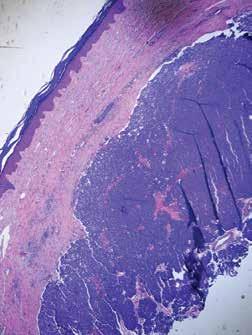

Merkel Cell Carcinoma, the Other Skin Cancer

When you mention skin cancer to the general public or even to the medical community, most folks think of the three big celebrities: basal cell carcinoma, squamous cell carcinoma, and melanoma. I like to refer to having occurrences of all three types of skin cancer in one patient as hitting the trifecta of skin cancer; unfortunately, there is no big payout with this trifecta. Excessive sun exposure is typically the common denominator. What is less known is there are other cancers of the skin besides the big three, and these can kill you as well. What I like to call “the fourth skin cancer” is the Merkel Cell Carcinoma. Not as famous as the big three, but Merkel cell carcinoma still should be treated with respect when it makes it rare appearances.

Merkel Cell carcinoma, like other skin cancers, has a predisposition for appearance in sun-exposed areas such as the face or sometimes the hands or digits. They usually do not appear in younger individuals and tend to arise more frequently in those with immunodeficiency. Merkel cell carcinomas present as a nonspecific papule or nodule. Because it can initially be misdiagnosed as a benign cyst, the actual pathology of the tumor may be delayed. Additionally, Merkel cell carcinoma is typically asymptomatic in the beginning, and this also adds to delay in diagnosis as many patients are not concerned until the fast-growing tumor reaches a large size.

The problem with Merkel cell carcinoma is that it is a highly aggressive type of skin cancer, and like melanomas, with enough growth and time, it can metastasize. Merkel cell carcinomas are treatable, and the treatment of choice is excision, the earlier, the better. Once a Merkel cell carcinoma has metastasized, it becomes a problematic tumor to treat, although new therapies are available that hold some promise. Recent studies suggest that 97% of Merkel Cell carcinomas have a common virus expression (Merkel cell polyomavirus). How this oncovirus may cause, Merkel cell carcinoma is currently unknown. Fortunately, patients that have Merkel cell carcinoma are not infectious.

If you observe a growth on the skin and you think to yourself, well, it doesn’t look like a basal or squamous cell carcinoma or melanoma; therefore, it’s probably benign always think of the other skin cancer, Merkel cell carcinoma. Happily, I have not had any of my patients that have had a trifecta of skin cancer also get Merkel cell carcinoma. In this scenario, I would have to name it the superfecta of skin cancer and not a title I would want to bestow on anyone.

FLORIDA MD - SEPTEMBER/OCTOBER 2023 7 DERMATOLOGY

Lucky Meisenheimer, M.D. is a board-certified dermatologist specializing in Mohs Surgery. He is the director of the Meisenheimer Clinic – Dermatology and Mohs Surgery. John Meisenheimer, VII is an MD practicing in Orlando.

Pathology of a Merkel cell carcinoma. BOTH PHOTOS: JOHN MEISENHEIMER, VII, MD A Merkel cell carcinoma of the finger.